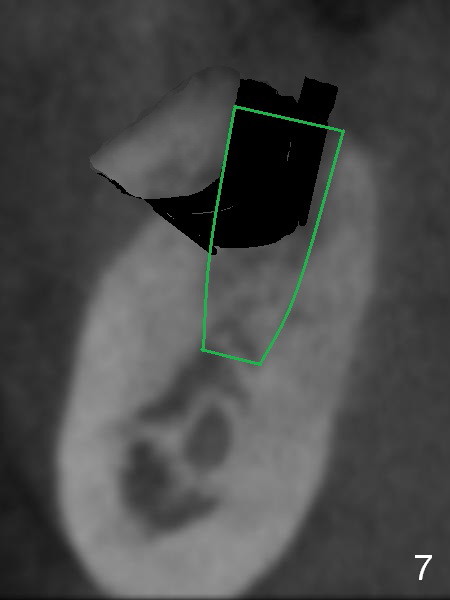

To preserve the coronal buccal plate, a two-staged ridge split will be performed. At the 1st stage, the ridge is to be sectioned as shown in red lines in Fig.5. Two to three weeks later, a chisel or bone expander will be used to pushed the sectioned segment buccally (Fig.6 yellow). As the osteotomy increases in depth and diameter and the implant as mentioned above (Fig.4) is placed (Fig.7 green), the segment is being pushed further, while it is still contacting the implant. One of the opposing dentition, #3 also needs implant.